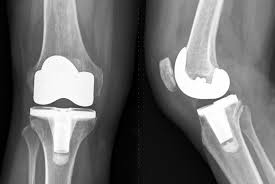

Accurate diagnosis forms the foundation of effective knee replacement surgery. Therefore, doctors conduct detailed clinical examinations supported by imaging studies such as X-rays and MRI scans. Moreover, functional assessments help determine how joint damage affects daily movement. In addition, surgeons develop individualised treatment plans based on joint alignment, muscle balance, and mobility expectations. Consequently, care remains personalised rather than standardised. This planning process strengthens patient confidence and supports predictable surgical outcomes.

Modern knee replacement surgery relies on refined surgical techniques to achieve precise joint alignment. Therefore, surgeons focus on controlled bone preparation and accurate implant positioning. Moreover, advanced instrumentation supports consistent execution throughout the procedure. In addition, standardised intraoperative protocols help maintain procedural efficiency and safety. Consequently, patients benefit from stable joint mechanics and improved functional performance. These surgical advancements contribute to reliable outcomes and enhanced joint durability.